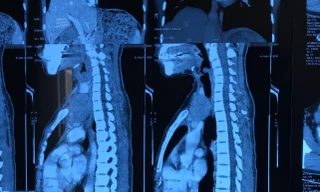

Sức khỏe Người phụ nữ Việt Nam bị ‘u đi lạc’, thế giới chỉ vài ca mắc TPO - Các bác sỹ Bệnh viện Ung Bướu Hà Nội vừa phẫu thuật cho một bệnh nhân nữ có u tuyến ức “lạc chỗ” ở tuyến giáp - một bệnh lý cực kỳ hiếm gặp.